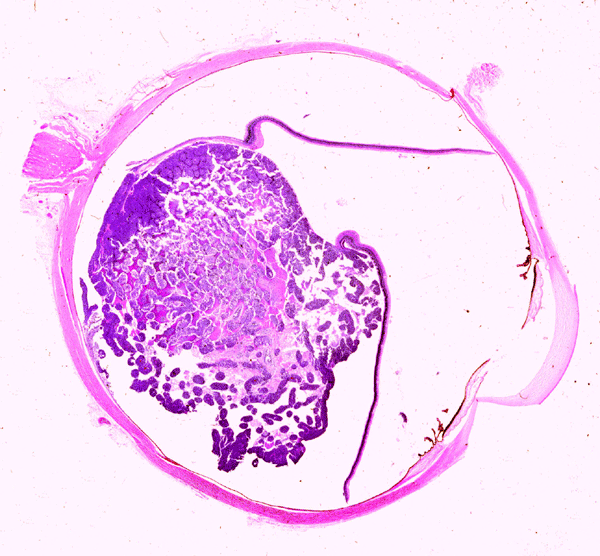

On the whole mount of the globe, there is an exophytic neoplasm that occupies about one-third the volume of the vitreous. The surface of the retina is free of tumor deposition (Panel A). The retina is detached by the mass. There are some pink, necrotic material at the core of the tumor (Panel B). On medium and high-magnification, the tumor is composed of densely packed small cells with hyperchromatic nuclei  without prominent nucleoli. A large number of the cells arrange in rossettes with a well-defined luminal border (Flexner-Wintersteiner rossettes) (Panel C and D). The tumor is confined within the globe and the optic nerve is free from invasion.

At the early stage, the tumor appears as a white nodule or multiple nodules (multicentric tumor) in the retina. The small nodules may suggest military tuberculosis involving the retina on fundoscopic examination. In bilateral cases, tumors often present simultaneously or with only a short time lag between tumors arising from the two globes.

As the tumor grow into a mass, some of them have an endophytic pattern that grows from the inner surface of retina into vitreous with tumor cells shedding into the vitreous. The tumor cells will disseminate and coat the retinal surface. As retinoblastoma in hereditary cases can be multicentric, such retinal coating should be distinguished from multifocal retinoblastoma. Retinal seeding is suggested if the tumor lies mainly on the surface or if clusters are seen within the vitreous.  Tumor cells from the vitreous may also reach the anterior chamber.

The exophytic type grows primarily from the outer retinal surface of the retina towards the choroids and is well illustrated in this case. The tumor will produce an elevation and then a detachment of the retina.  From the choroids, tumor cells invade into the orbit and conjunctiva. Extraocular extension and metastasis will follow.  Neither of these patterns carry a prognostic significance. A mixed pattern that consists of both the endophytic type and exophytic type is perhaps the most common type.